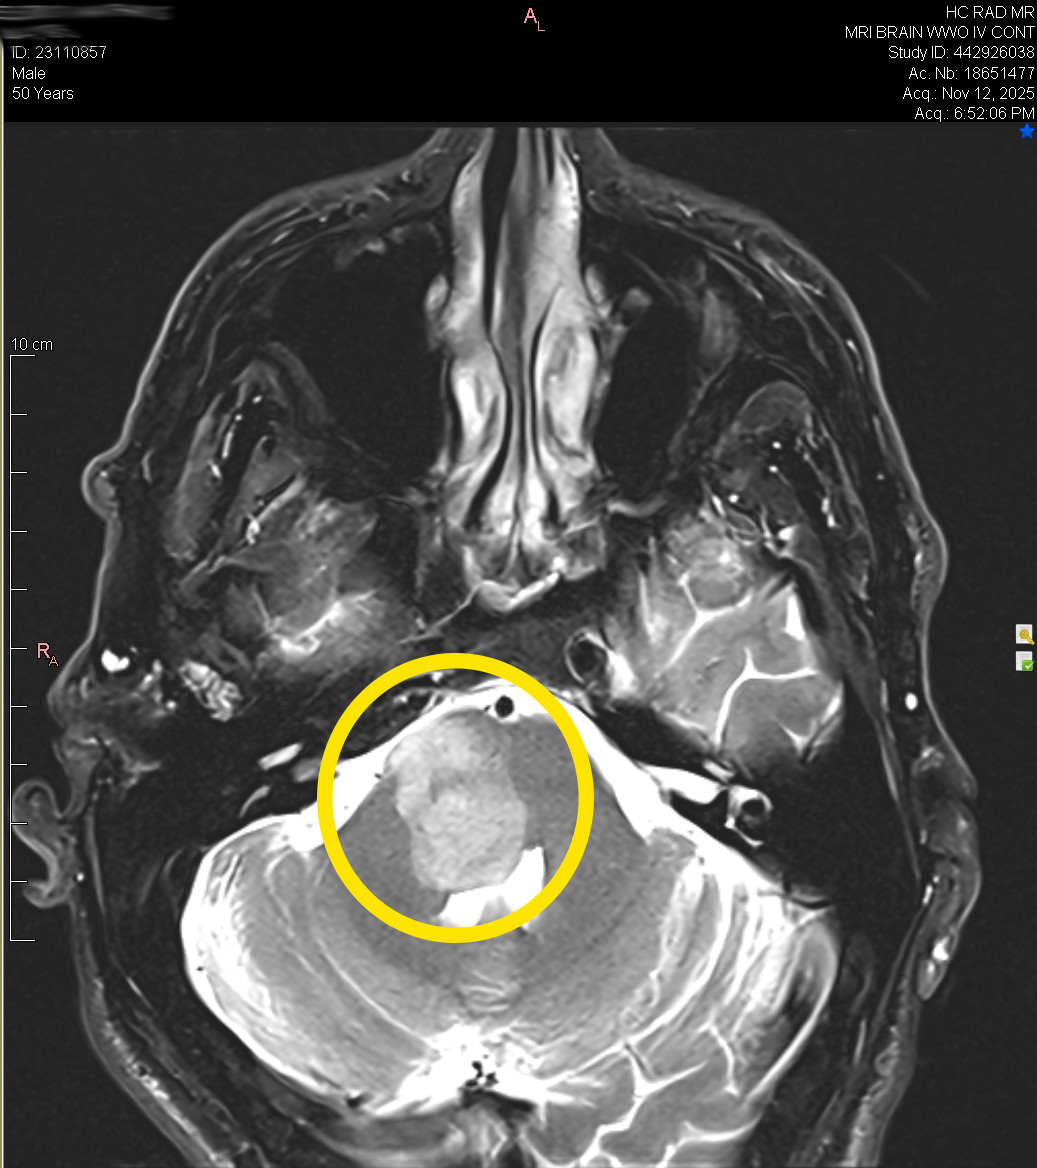

I have an inoperable growth on my brainstem.

Because of its location, surgery is not an option.

This growth is pressing on key cranial nerves, causing vertigo and other neurological symptoms, making it impossible for me to work full-time or travel like I used to. I can teach from home in short bursts, but even that often leaves me exhausted.

Recently, however, follow-up imaging has shown that the growth has begun to increase in size again, for reasons my team and I are still working to uncover. This means we need to adjust the strategy so the abnormal cells can’t adapt and we can finally resolve this at the root.